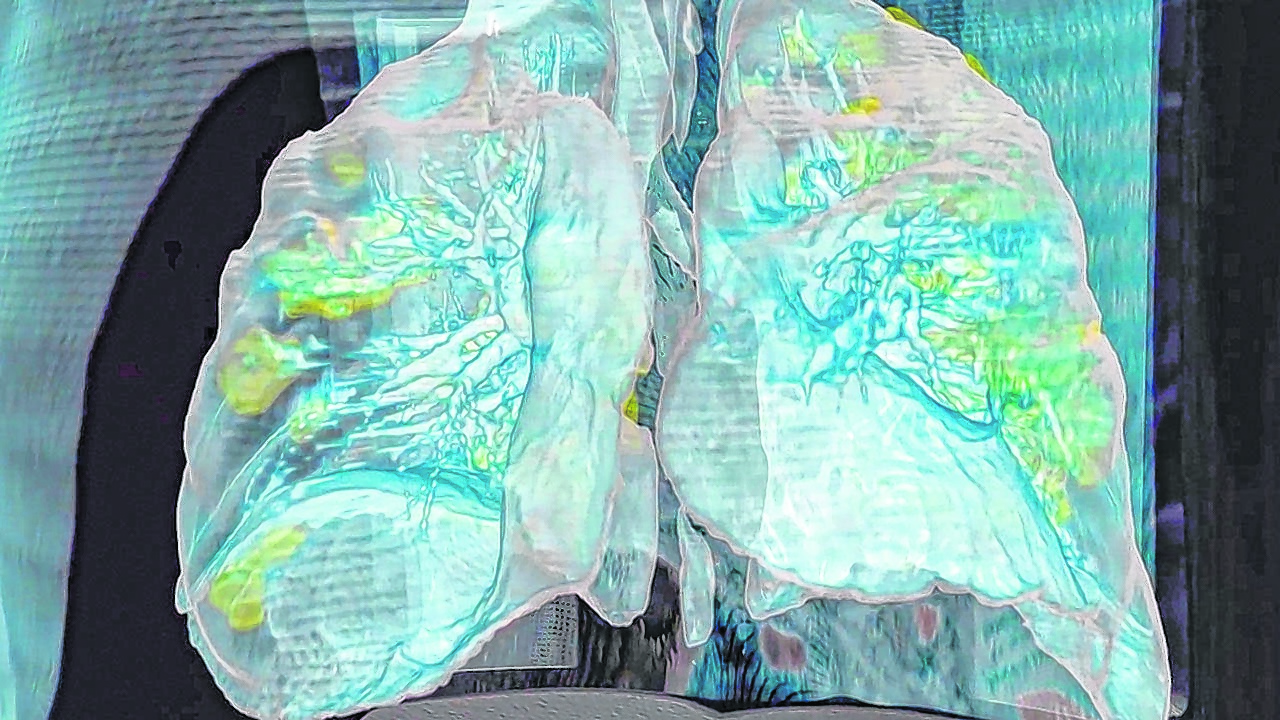

¿Cómo mata el coronavirus? Se sabe que los pulmones son el blanco mortal preferencial del covid-19, pero otros órganos igual de vitales como el corazón, los riñones, el cerebro, los intestinos, el hígado y hasta los ojos se están revelando también en víctimas directas del ataque del virus una vez que está dentro del cuerpo.

Todo indica que el motivo de esa dispersión de los daños dentro del cuerpo son los receptores de superficie celular ACE2, presentes en abundancia en el revestimiento de las células de varios tejidos diferentes, entre ellos los de los pulmones, arterias, corazón, riñón e intestinos.

Normalmente la invasión comienza en la nariz y garganta al inhalar la persona una cantidad indeterminada de virus. La mucosa nasal interna está tapizada de células ricas en ACE2. Si la infección no es detenida ahí por el sistema inmune, desciende rápidamente a los pulmones donde todo se puede complicar gravemente.

Pero también es posible -lo están refiriendo miles de ‘papers’ y documentos publicados desde que comenzó la epidemia en China- que el virus se dirija al tejido cardíaco, renal, red arterio-venosa y cerebro, entre otros blancos vitales.

Los estudios realizados en medio de una lucha que es por la vida, muestran trazos de la presencia del virus en todos esos órganos o sistemas. Biopsias, radiografías, resonancias magnéticas, modelos en 3D y escáneres dan cuenta de un daño brutal pero misterioso en sus causas.